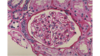

What is shown here?

renal cortex

note the glomeruli everywhere

also DCT & PCT will be prevalent. PCT will be the ones w/ the fuzzy lumen.